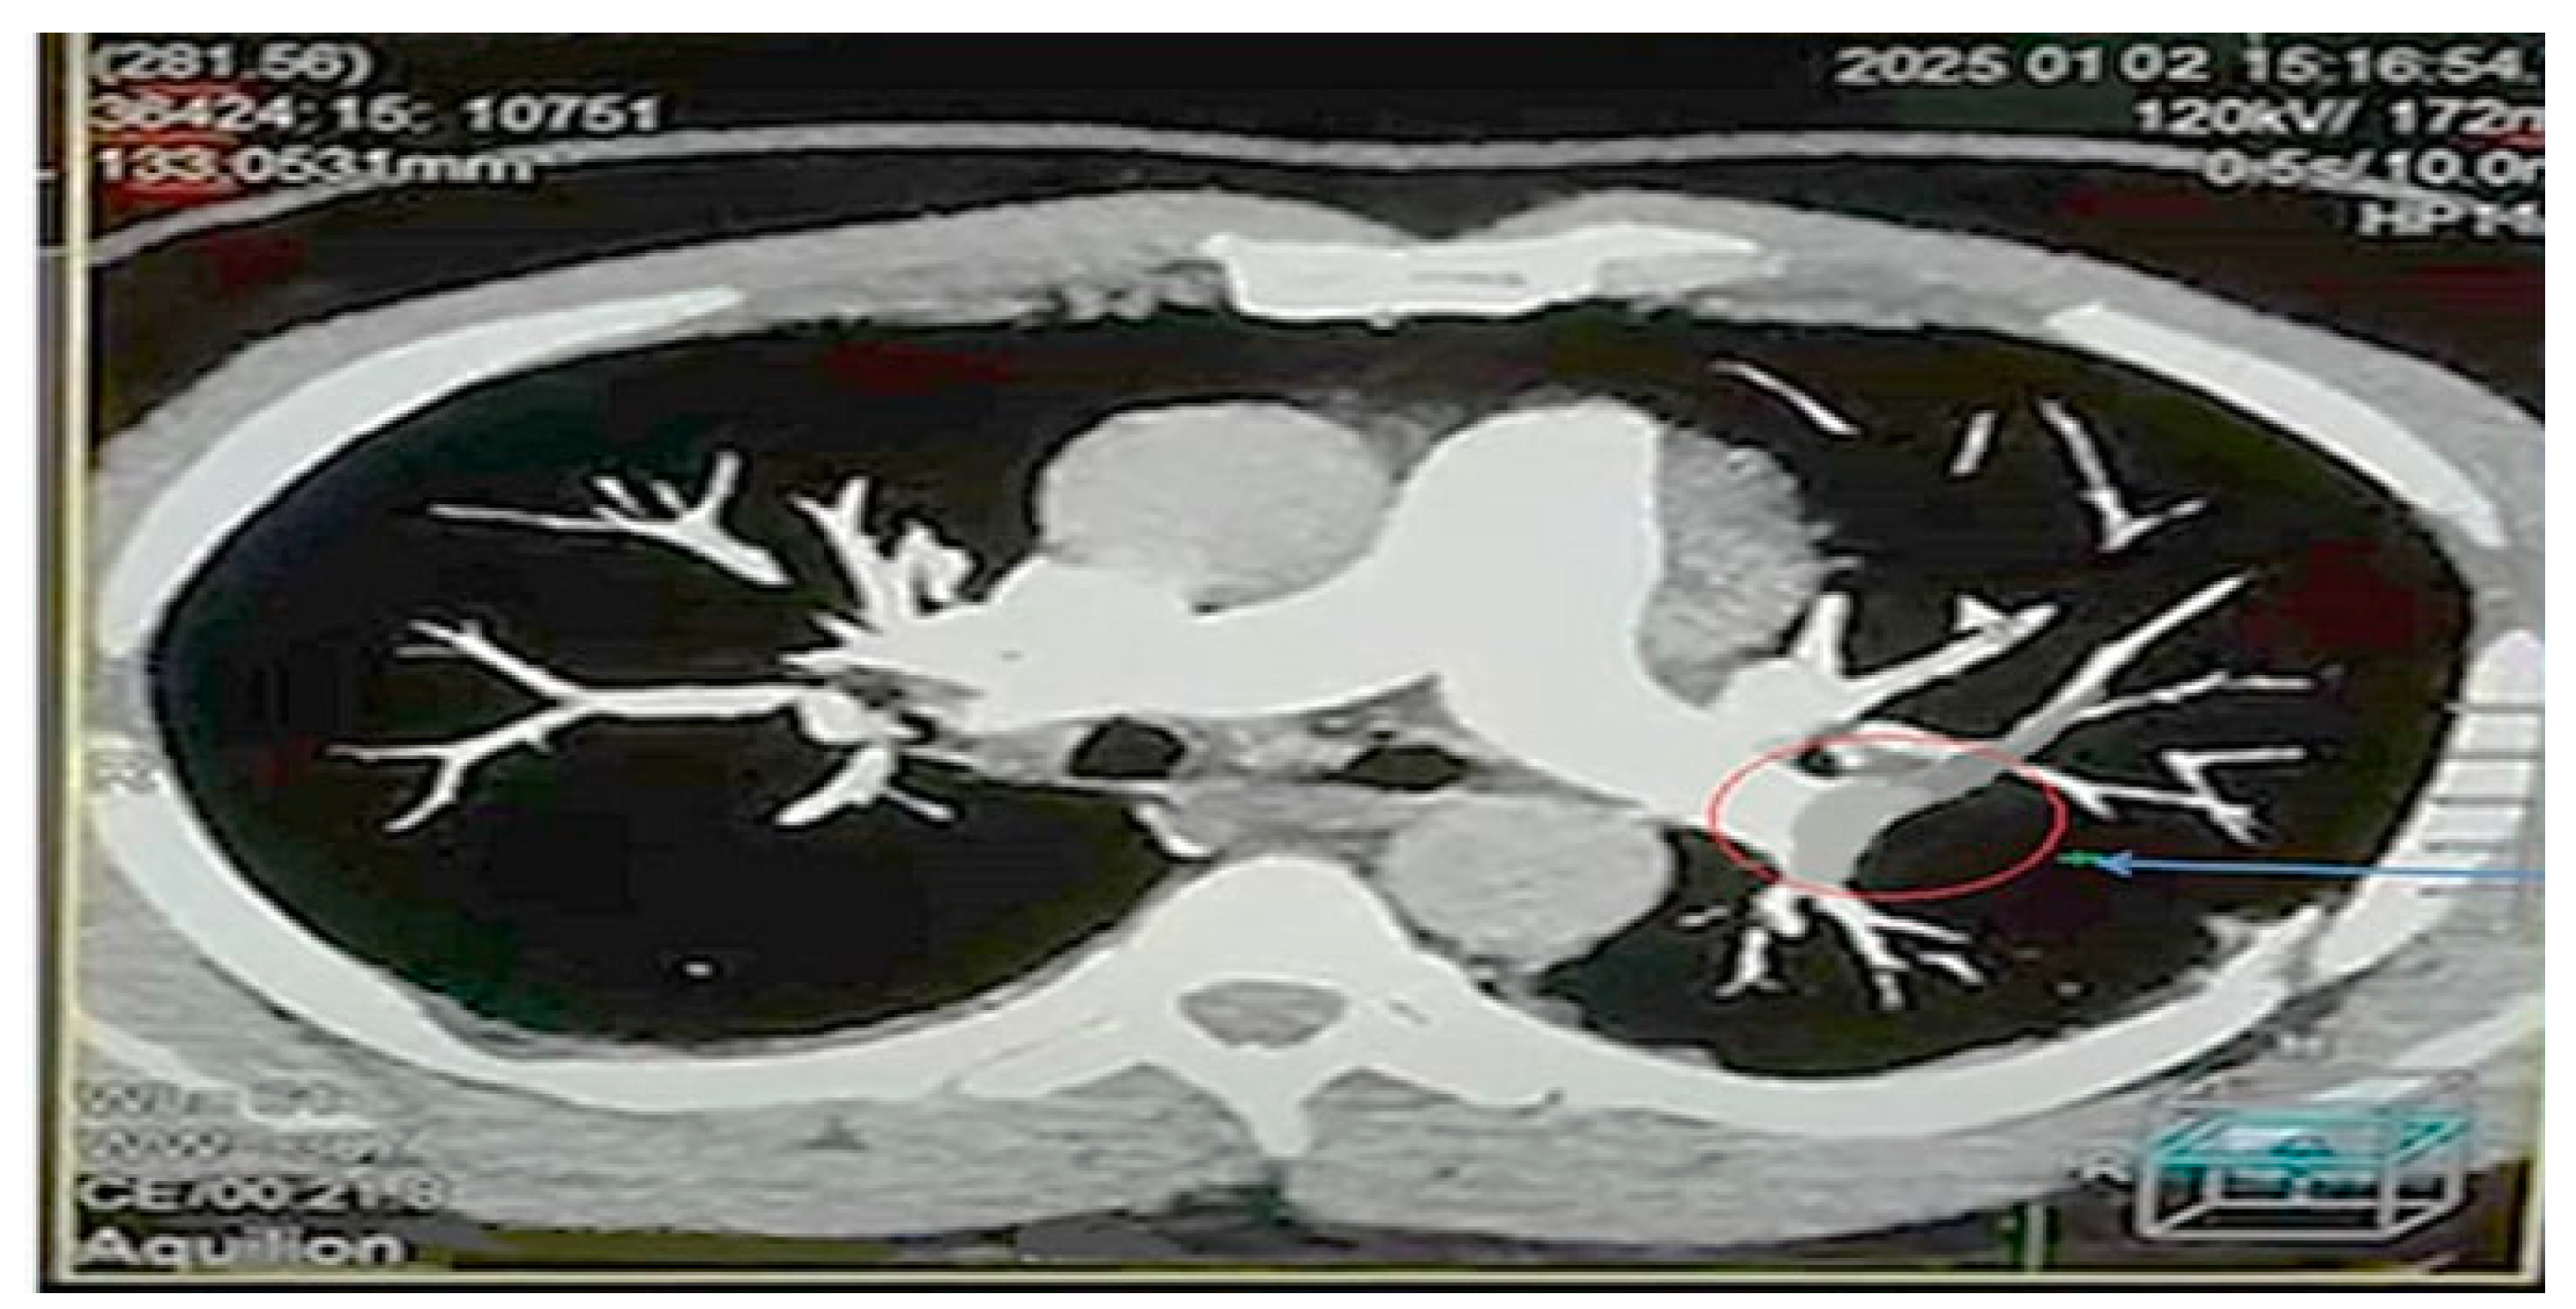

4.6. Visual Findings and Clinical Implications